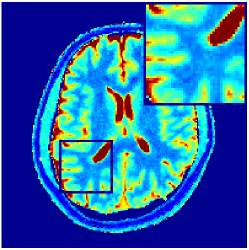

VI-E In-vivo experiments

Two sets of experiments were conducted here: first, we used the 2D and 3D acquisition sequences for scanning a healthy volunteer’s brain (real-world acquisitions). Figures 6 and 7 display the parametric maps reconstructed from 2D spiral and radial readouts. We computed the T1, T2 and proton density (PD) maps using baseline reconstruction algorithms ZF, VS, LR, FLOR, AIR-MRF and our proposed LRTV. While baselines use DM either for quantitative inference or also during reconstruction (i.e. AIR-MRF), we further compare the DM-free LRTV’s performance when cascaded to DM, KM and MRFResnet for quantitative inference. For the 3D spiral acquisitions we compared LRTV and its closest competitor VS in Figure 8. Outcomes from other tested algorithm are displayed in the supplementary materials (Figure S5). Since FLOR does not use dimensionality-reduction, our system ran out of memory during 3D reconstruction; hence results are not reported in this case.

VI-E1 Discussion

The LRTV-DM and LRTV-MRFResnet perform on par, and both outperform all tested baselines for reconstructing T1, T2 and PD maps in all acquisition schemes. This can be observed both visually in Figures 6, 7, 8, S2 and S3, and quantitatively in Table IV across all tested metrics. Other baselines were unable to successfully remove the under-sampling artefacts in TSMIs, and these errors propagated to the parameter inference phase and resulted in inaccurate maps. Temporal-only priors incorporated within LR are shown insufficient to regularise the inverse problem and LR sometimes (e.g. 2D spiral acquisitions) can admit solutions with even stronger artefacts than the model-free ZF baseline. This issue was previously studied for other non-Cartesian MRF readouts that similar to our spiral/radial trajectories, miss to sample the corners of the k-space in all timeframes (see section 2.2.2 and figure 2 in [19]). In the absence of reference for the k-space corners information, the LR iterations despite minimising the objective can converge to solutions with high-frequency artefacts, as visible in the computed maps. This highlights the need for adding an appropriate spatial-domain regularisation. FLOR reduces the LR’s artefacts but this improvement is limited because the suggested nuclear norm penalty does not incorporate an explicit spatial regularisation. Further for reducing artefacts, FLOR can introduce an undesirable bias in the computed T1/T2 maps e.g. see error maps in Figures S2 and S3. The non model-based VS baseline incorporates spatial regularisation and results in spatially smoother maps than ZF and LR, but it is unable to output artefact-free images. Further and consistent with our in-vitro experiment, we observe that VS overestimates the T2 values (e.g. in White and Grey matter regions) in tested 2D acquisitions i.e. the spatial regularisation trades off agains the quantification accuracy. The model-based AIR-MRF adds spatial regularisation through 2D/3D low-pass Gaussian filters however this trades off the sharpness of the computed maps and can increase the errors at the tissue boundaries (we searched Gaussian spreads that keep the blurs and high-frequency artefacts minimal). For our acquisition readouts, Gaussian filters performed better than disk filters of [19] for avoiding strong Gibbs artefacts. On the other hand, the spatiotemporally regularised LRTV greatly improves the TSMI reconstructions i.e. 4 dB enhancement compared to the closest competitor baseline (Table IV). This enables computing accurate and aliased-free multi-parametric inference using DM or the DM-free learning-based alternative MRFResnet as visible in Figures 6, 7, 8, S2 and S3. MRResnet and DM score competitive quantitative inference results i.e. T1 and T2 MAPE less than 5% and 9%, respectively (Table IV). KM also outputs comparably accurate T1 maps, however this shallow learning model despite having a model size larger than MRFResnet, is unable to learn accurate T2/PD quantification and it results in poor estimated maps, consistent with our observations in section VI-C.